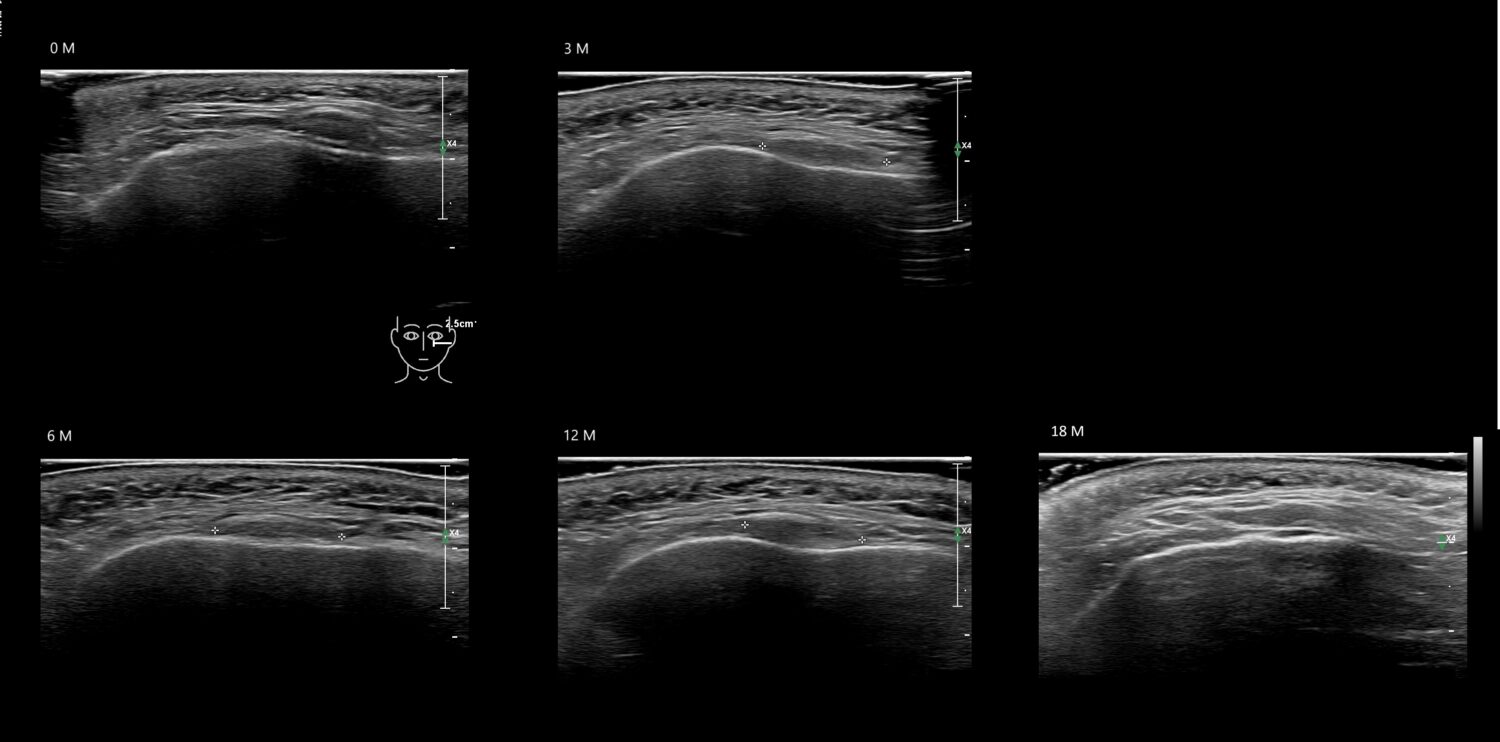

Fillers

Draw in the second image below where the fillers are located. To check if your answer is correct, swipe the first image to the right.